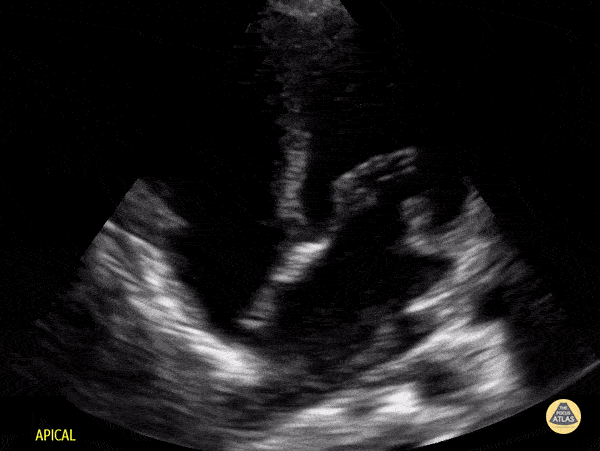

Peds-Cardiac - Older Kid Apical 4 Chamber

Normal apical 4 chamber view in a 4-year-old preschooler. Contributor: Jaron Smith, MD, Phoenix Children's Hospital